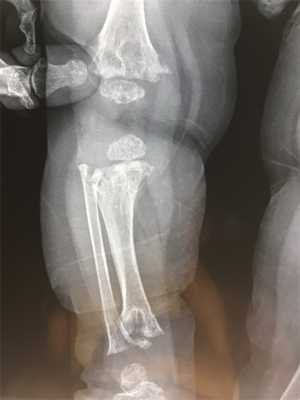

- второй тип, с преобладанием бедренного компонента: деформация шейки бедра (антеторсия либо вальгусная деформация — см. рис 1-2); вертлужная впадина поражена незначительно, либо ее развитие нормальное;

Рис.1Нормальная торсия [3]

Рис.2 Антеторсия [3]